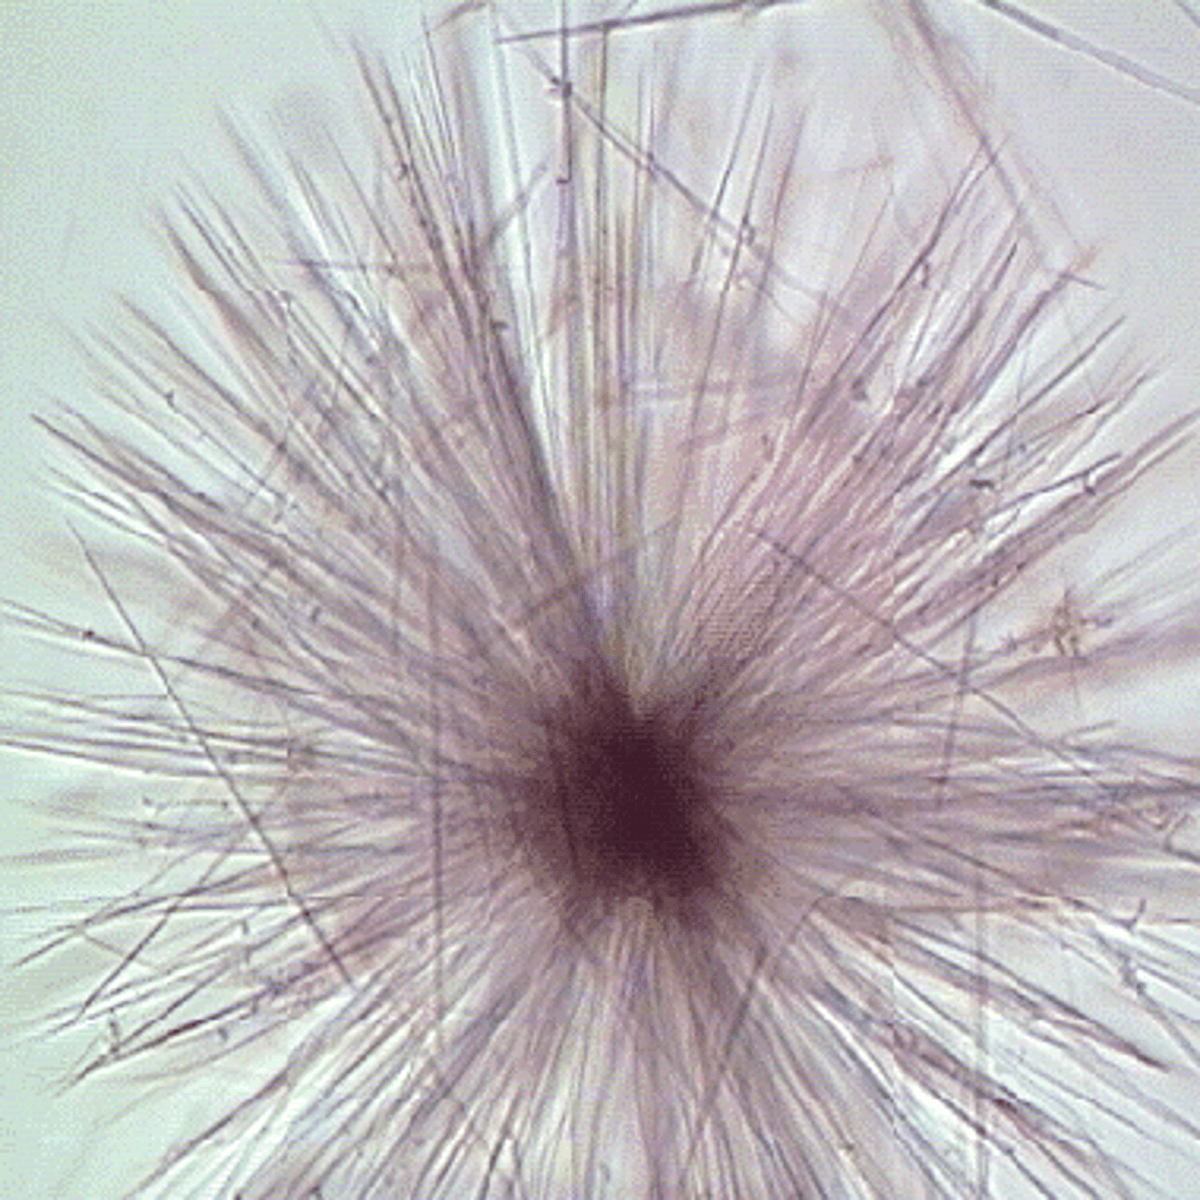

oval fat body

Many bulbs

Confirmed with lipid stains